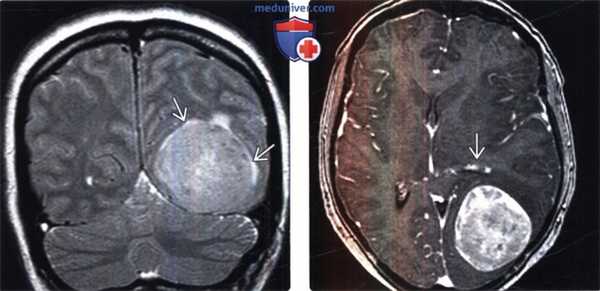

(Слева) Бесконтрастная КТ, аксиальный срез: определяется дольчатое гиперденсное объемное образование, расположенное по ходу намета мозжечка справа.

(Справа) МРТ, FLAIR, аксиальный срез: у этого же пациента визуализируется гипоинтенсивное многодольчатое объемное образование с перифокальным отеком и масс-эффектом на IV желудочек.

(Слева) МРТ, Т2-ВИ, корональный срез: у мужчины 47 лет определяется внемозговое образование однородной структуры с четкими контурами с минимальным отеком.

(Справа) МРТ, постконтрастное Т1 -ВИ, аксиальный срез: у этого же пациента визуализируется интенсивное относительно однородное контрастное усиление. Обратите внимание на компрессию треугольника левого бокового желудочка. Несмотря на отсутствие агрессивных рентгенологических признаков при хирургической резекции и гистологическом исследовании была диагностирована злокачественная Менингиома grade III. Для окончательного установления гистологического типа и степени злокачественности менингиомы необходима биопсия.